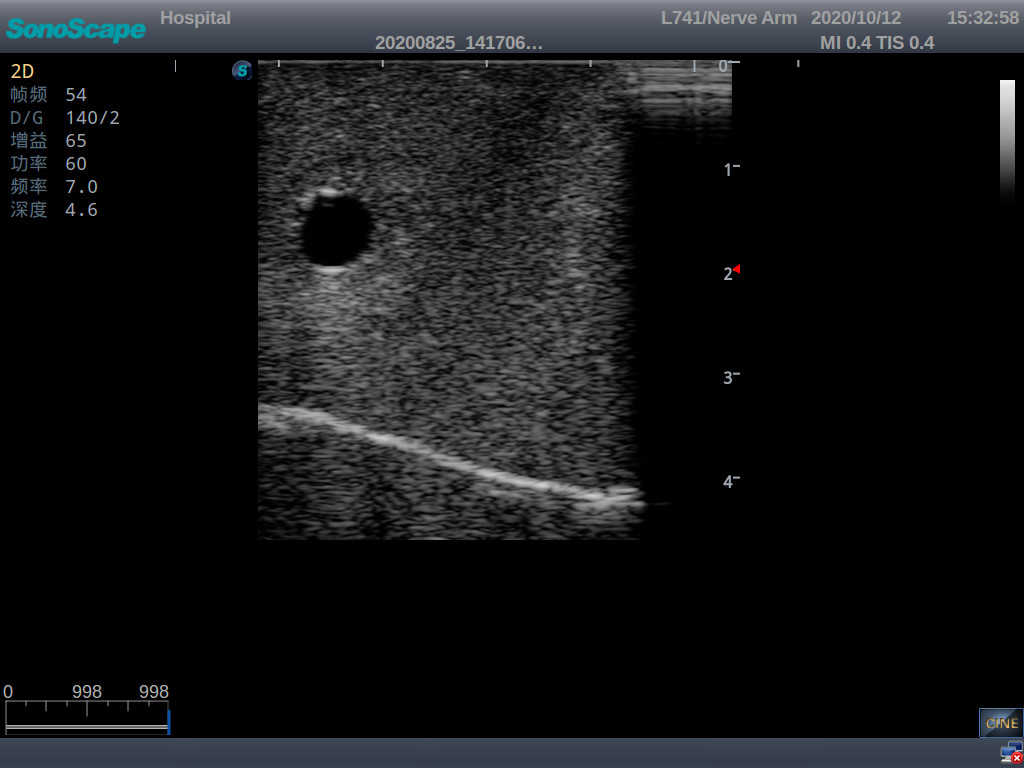

3) The puncture pad at the arm is made of high-molecular ultrasound material, close to real skin. It can support the use of real ultrasound machines, and the images of tissue structures (skin, subcutaneous tissue, blood vessels) under ultrasound are clear and real

5) The guide wire’s march can be observed under the guidance of ultrasound, and also whether the catheter is placed correctly can be detected